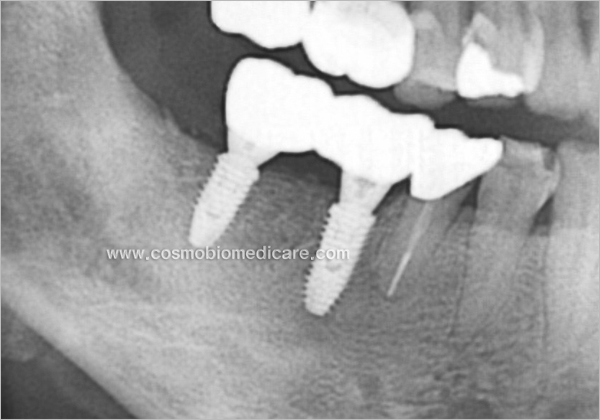

Clinical Cases

• Case1

• Case2

• Case3

• Case4

• Case5

• Case6

• Case7

• Case8

• Case9

• Case10